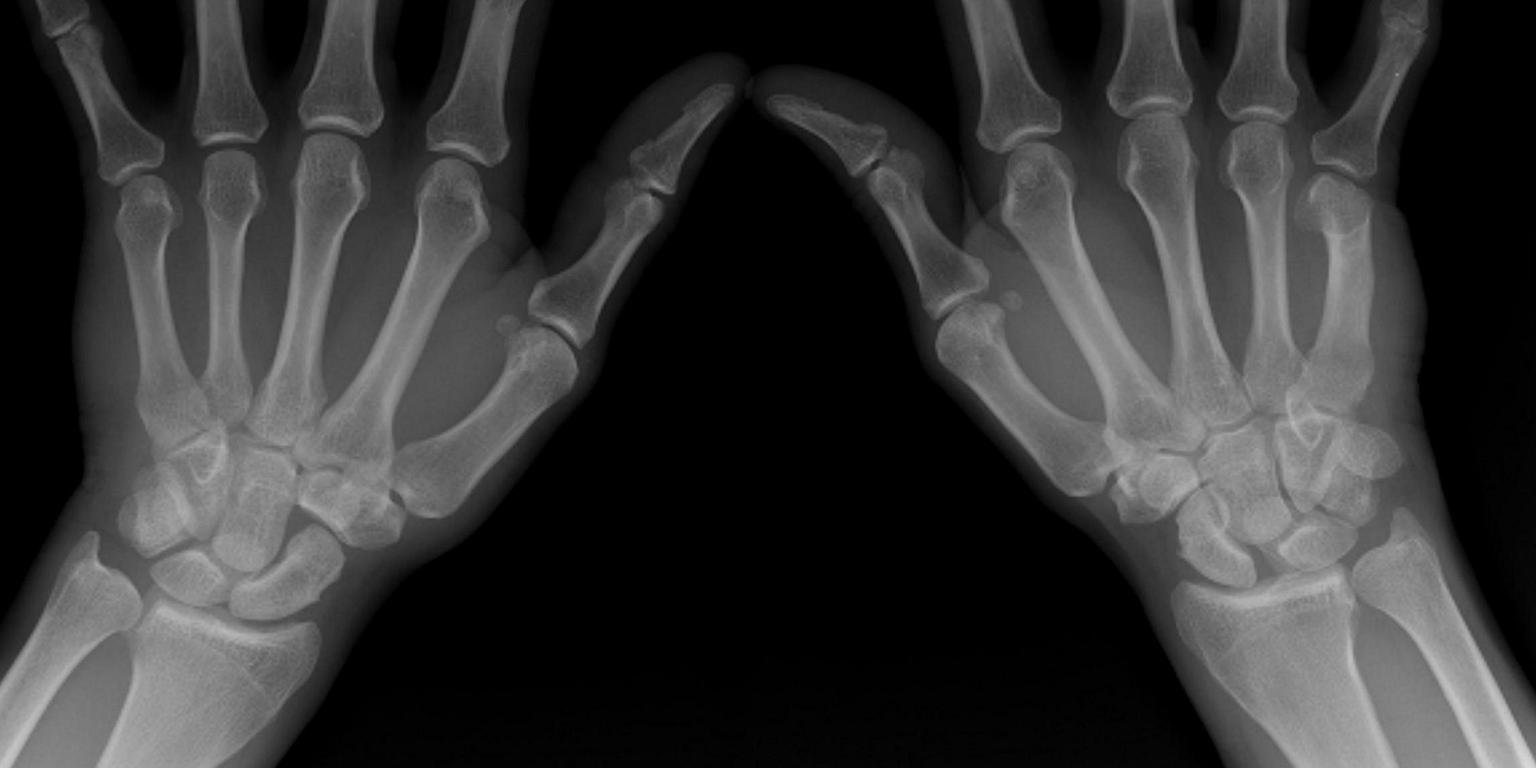

Fysiotherapeutische beoordeling van gesloten polstraumata (VI)

Dit artikel beschrijft de meest voorkomende gesloten polsletsels waarmee de algemeen fysiotherapeut in aanraking kan komen. Het doel is om een beknopt overzicht te geven van de diverse polspathologieën en om directe handvatten te bieden voor de diagnostiek. Op die manier kan de fysiotherapeut weloverwogen besluiten of de patiënt door een gespecialiseerde professional (handtherapeut en/of handchirurg) moet worden gezien om genuanceerde diagnostiek mogelijk te maken.

Fysiotherapeutische beoordeling van gesloten polstraumata

Fysiotherapeutische beoordeling van gesloten polstraumata